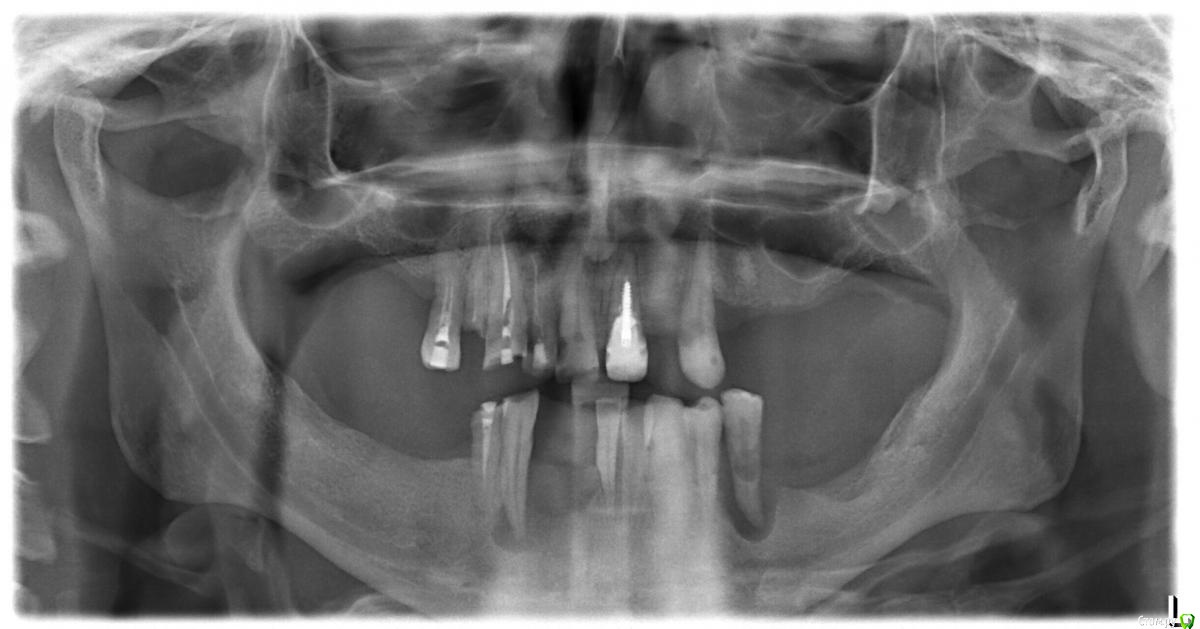

drUspex Опубликовано 16 сентября, 2017 Автор Поделиться Опубликовано 16 сентября, 2017 (изменено) Вот снимок до удаления зубов Изменено 16 сентября, 2017 пользователем drUspex Ссылка на комментарий

ReaperGanzA Опубликовано 17 сентября, 2017 Поделиться Опубликовано 17 сентября, 2017 1-Если подойти критично к верней челюсти, то по снимку там ни одного зуба способного нести нагрузку2-Шаровидный атачмены на зубах это архаизм, в данном случае я бы изготовил иммедиат протез(с удалением всего) на вч на 3 месяца, потом заменил на постоянный и прогнозируемо получил был отличный псп с фиксацией лучше чем на шариках и равномерной нагрузкой на ложе.3-Ремонтопригодность протеза с шариками на зубах сомнительна, много времени, много геморроя, ибо опорные зубы буду уходить так или иначе4-Найдите хорошего съемщика на выполнение таких работ, это не рядовая работа, если примерка в порядке а протезы шляпа, то техник ошибается на этапе паковки скорее всего, причин может быть масса и лучше сначала поработать с хорошим техником чтобы исключить проблемы на техническом этапе5- из советов: прикус на жестком базисе здесь не нужен, нужно чтобы он перекрывал и опирался на шарики; когда вам приходит протез под перебаз прямым методом, то пилите его под матрицы не на обум а точечно, одеваете на шарики матрицы, вносите базу спидекса-немного внутрь протеза и прикладываете к матрицам, по отпечаткам очень осторожно выпиливаете места для матриц, смотрите протез в прикусе и по возможности перебазируете под жевательным давлением. Чтобы это все выполнить низ должен быть стабилен и протез вч тоже даже когда нет опоры в области матриц до перебаза Ссылка на комментарий

drUspex Опубликовано 17 сентября, 2017 Автор Поделиться Опубликовано 17 сентября, 2017 1- в данной конструкции задача опорных зубов удерживающая, жевательная нагрузка должна распределяться на мягких тканях. Соответственно, чтобы облегчить пациенту привыкание к первым в жизни протезам, да ещё и пспп, я и решил прибегнуть к сохранению не идеальных, но вполне способных некоторое время удерживать протез, зубов. Пациент осведомлён о временном характере такого протезирования и дал своё добро.2- к сожалению нет фото протезного ложа, сделаю при первой возможности. Там очень неравномерная атрофия, небо неплохое, думаю, что можно добиться средненькой фиксации без аттачменов. Согласен, с аттачменами много возни, но в моей практике они себя как правило оправдывали. Даже 1,5- 2 года службы это уже большое дело для процесса адаптации пациента к пспп, я так думаю). Аттачмены в свои зубы - Архаизм , если альтернатива - установка имплантатов. а удаление всего и изготовление пспп... здесь не меньше недостатков, только уже для пациентов. 3- по поводу ремонтопригодности в чем сложность перебазировать протез через месяц после удаления , далее контроль через 3,6,12 месяцев? 4- я бы грешил на техников, если бы не ситуация с перебазировками. Как бы неправильно не был зарегистрирован прикус, после перебазировки протез должен без баланса сидеть (не говорю держаться) на протезном ложе . Я с ними делал похожие работы, раньше не было таких проблем. Что может быть причиной такого? У меня подозрение только на расположение зубов. У кого есть другие варианты?5- перед прямой перебазировкой выпиливаю пространство для матриц под контролем жидкой копирки(О-spray) + расширяюсь немного для пластмассы. Думаете с жесткими базисами регистрация цс точнее не будет?1-Если подойти критично к верней челюсти, то по снимку там ни одного зуба способного нести нагрузку2-Шаровидный атачмены на зубах это архаизм, в данном случае я бы изготовил иммедиат протез(с удалением всего) на вч на 3 месяца, потом заменил на постоянный и прогнозируемо получил был отличный псп с фиксацией лучше чем на шариках и равномерной нагрузкой на ложе.3-Ремонтопригодность протеза с шариками на зубах сомнительна, много времени, много геморроя, ибо опорные зубы буду уходить так или иначе4-Найдите хорошего съемщика на выполнение таких работ, это не рядовая работа, если примерка в порядке а протезы шляпа, то техник ошибается на этапе паковки скорее всего, причин может быть масса и лучше сначала поработать с хорошим техником чтобы исключить проблемы на техническом этапе5- из советов: прикус на жестком базисе здесь не нужен, нужно чтобы он перекрывал и опирался на шарики; когда вам приходит протез под перебаз прямым методом, то пилите его под матрицы не на обум а точечно, одеваете на шарики матрицы, вносите базу спидекса-немного внутрь протеза и прикладываете к матрицам, по отпечаткам очень осторожно выпиливаете места для матриц, смотрите протез в прикусе и по возможности перебазируете под жевательным давлением. Чтобы это все выполнить низ должен быть стабилен и протез вч тоже даже когда нет опоры в области матриц до перебаза Ссылка на комментарий